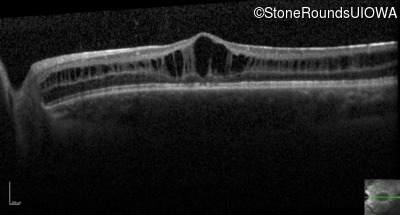

Optical Coherence Tomography - Right - 20/63 -2

Exemplar / OCT Stack

OCT Stack